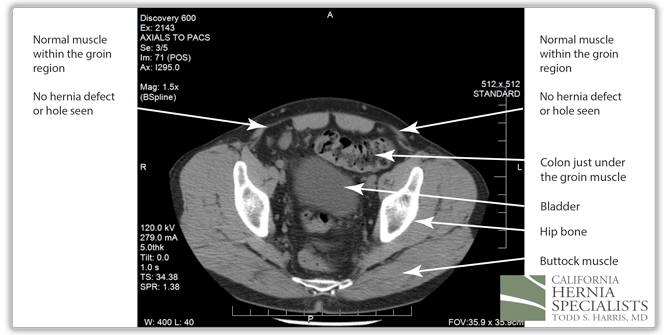

The CAT scan image above shows normal muscles of the abdominal wall with no evidence of a hole, or a hernia.

However, in this CAT scan image, there is a noticeable hole in the lower muscle wall, and the start of an inguinal hernia both on the left and the right side of the groin.

The bladder can be seen squeezing through the hole in the muscles within the patients right groin (left side of the CAT scan image). On the patients left side (right side of the image), there is only fat pushing through the hernia defect.

At the bottom of the hernia, the bladder on the right side was attached to the patients right testicle, and was pushing the base of the penis to the left side. When the patients bladder was full, he noticed severe pain in the groin, and difficulty urinating.

The patient underwent a laparoscopic bilateral inguinal hernia repair. During the surgery, the bladder was pulled out of the right groin hernia, and the fat was pulled out of the left hernia. Laparoscopic hernia mesh was placed to repair both groins. Due to the fact that the bladder was so close to the hernia repair, a bladder catheter was left in place for 2 weeks after the surgery to ensure complete healing.